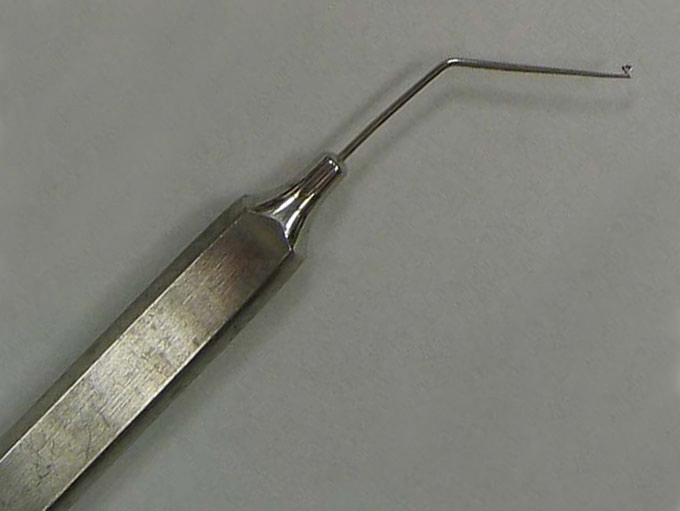

Kuglen Hook, angled, round handle

Angled Kuglen

Catalog: Katena K3-5523

Typical Use(s): Position IOL and haptics; Fix eye with paracentesis; Retrieve suture from AC

Kuglen Hook, angled, round handle (Enlarged)

Angled Kuglen

Catalog: Katena K3-5523

Typical Use(s): Position IOL and haptics; Fix eye with paracentesis; Retrieve suture from AC